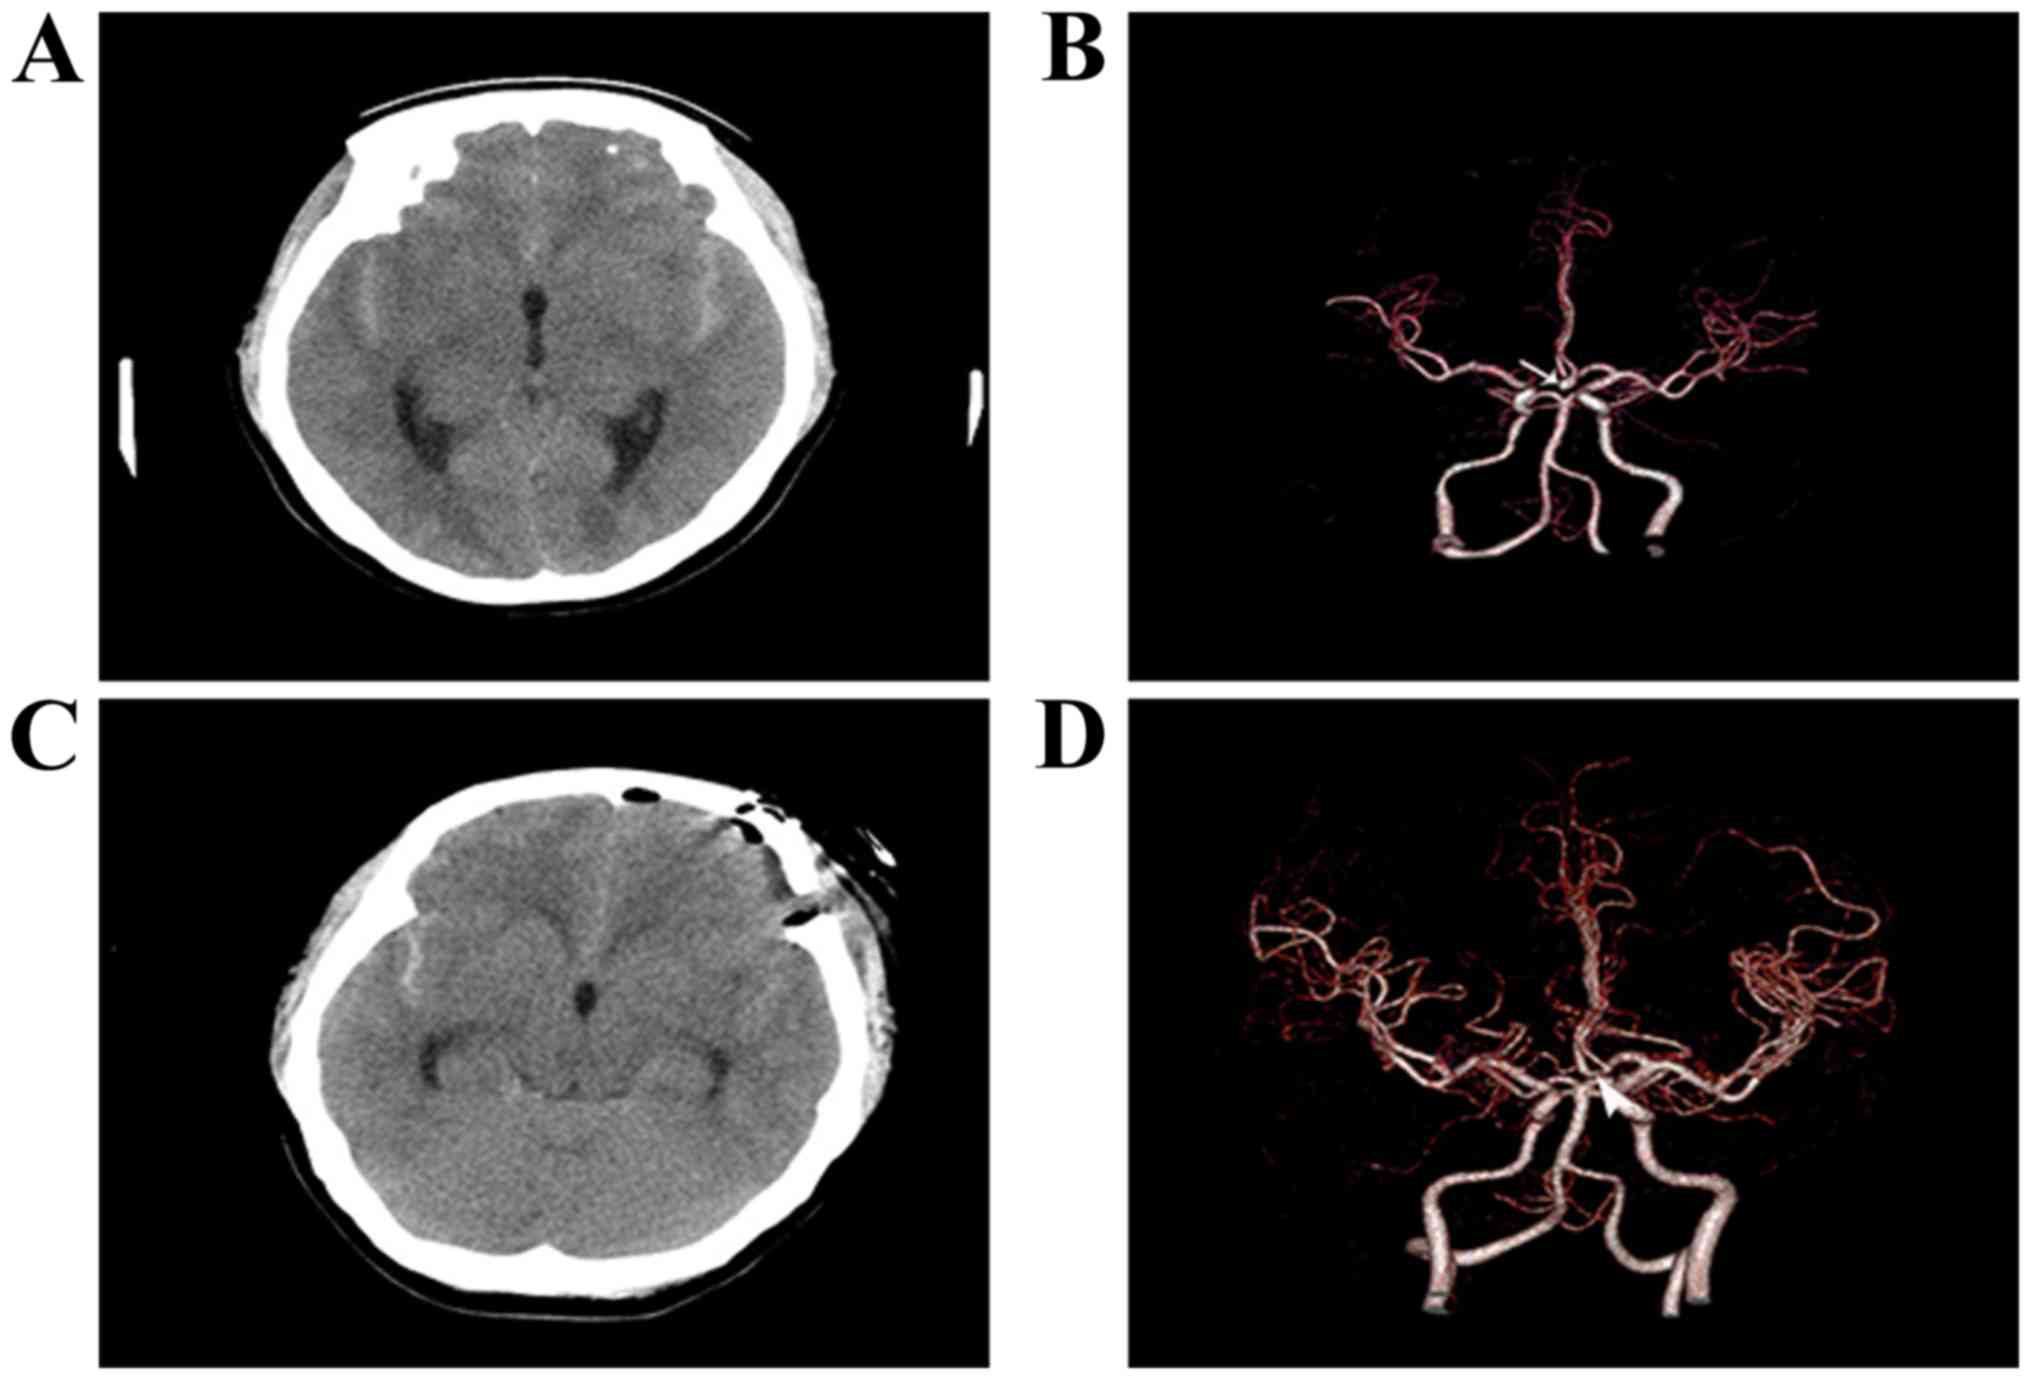

CT and CT angiography of 42-year-old female presenting with a headache and decreased consciousness disorder. (A) Pre-operative CT with subarachnoid hemorrhage. (B) Pre-operative CT angiography (white arrow indicates the aneurysm). (C) Postoperative CT with clipped aneurysm. (D) Post-operative CT angiography displaying complete clipping of the anterior communicating artery aneurysm via supraorbital eyebrow keyhole approach (arrowhead).

CT and CT angiography of a 29-year-old female presenting with a headache and vomiting. (A) Pre-operative CT with subarachnoid hemorrhage. (B) Pre-operative CT angiography (white arrow indicates the aneurysm). (C) Postoperative CT with clipped aneurysm. (D) Post-operative CT angiography displaying complete clipping of the anterior communicating artery aneurysm via supraorbital eyebrow keyhole approach (arrowhead).